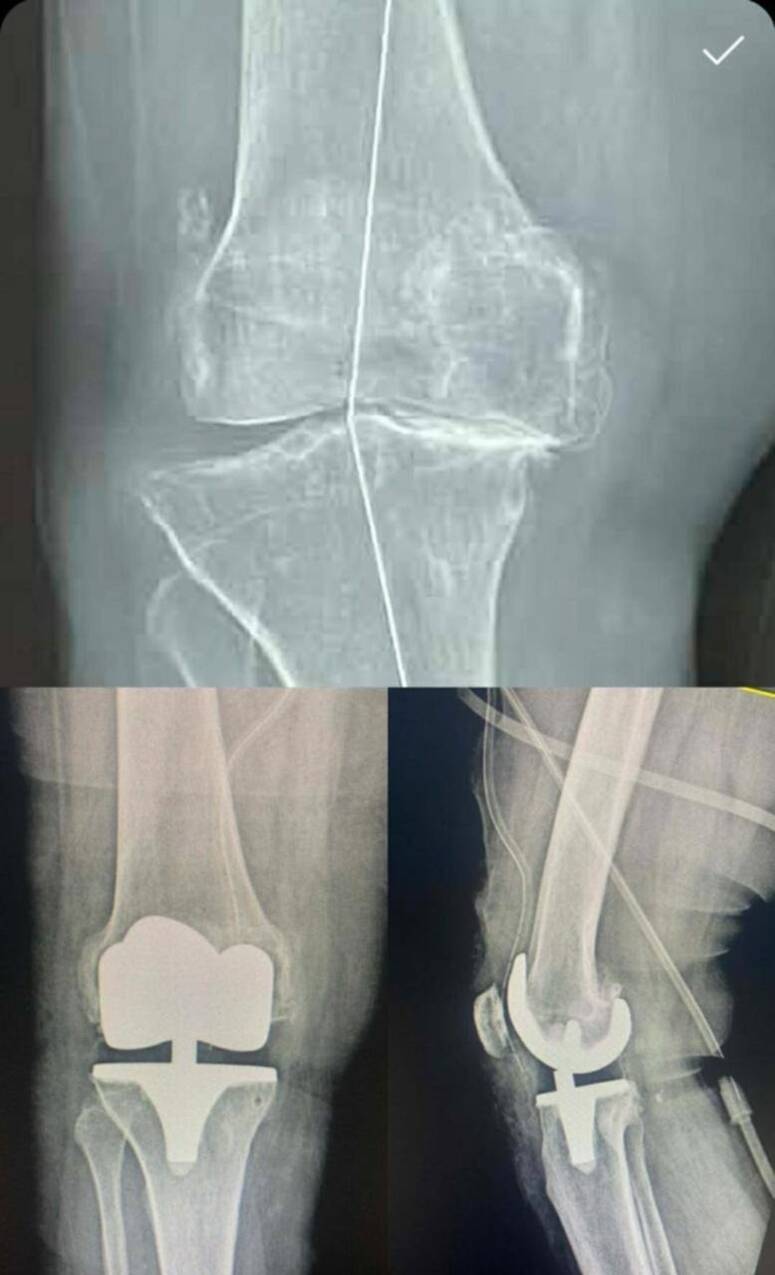

جندوبة: نجاح أوّل عملية تركيب مفصل اصطناعي كامل بالمستشفى الجهوي بجندوبة

نجح فريق طبي بالمستشفى الجهوي بجندوبة، أمس الجمعة، في إجراء أول عملية جراحية دقيقة لتركيب مفصل اصطناعي كامل للركبة بالمؤسسة، لفائدة مريض يعاني من داء مفصل الركبة في مرحلة متقدمة (الفصال العظمي الشديد).

ووفق المدير الجهوي للصحة بجندوبة، خليل الغجاتي، فإنّ هذه العملية تعتبر أولى ثمار إضفاء الصبغة الجامعية على قسمي التخدير والإنعاش بالمستشفى الجهوي بجندوبة مطلع الشهر الجاري، ونتيجة لتوفر طاقم طبي مختص قادر على إجراء تدخلات ناجعة ومعالجة أمراض كانت تُحال سابقا إلى المستشفيات المركزية بالعاصمة، والتي تتطلب عادة آجال انتظار طويلة.